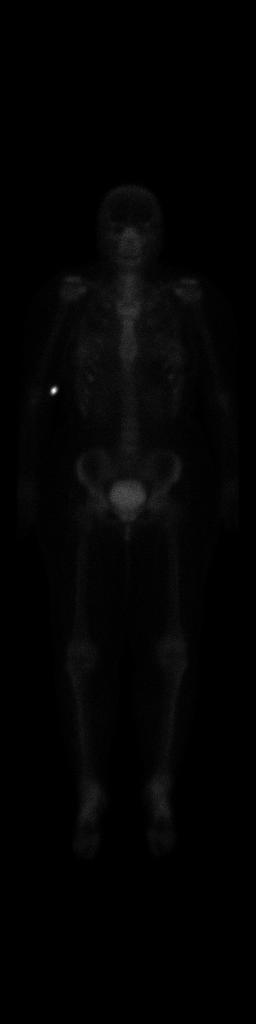

On October 23rd 2023 a series of medical exams started for me. The overall goal was to exclude cancer metastases in my body and to understand a bit better the general status of the disease. I started with a bone scan scintigraphy. It went down more or less like this: I was injected a radioactive substance, then sent home for a few hours, where I was allowed to eat and I had to drink a lot of water, the more, the better. For the exam to take place, the bladder needs to be empty (a full bladder can obscure the pelvis and the surrounding pelvic bones), so they asked me to pee right before getting on the table. The exam lasted around 45 minutes, which seemed an eternity as in the middle of it I realized I had to pee again, and I obviously couldn’t. Also, the camera moved very very close to my face without touching it: overall, an horrible experience. A few days later I had the results: the medical report stated that there were “no arguments for bone metastases”.

You can see some points in my body lighting up, but apparently this was not related to cancer. Fun fact: I remember the technician in the room asking me to try and focus and not piss myself on the table (because apparently this can happen). They said something like: “there’s no shame in it, but I really don’t want you to have to do this all over again.” Yeah, I didn’t want that either.